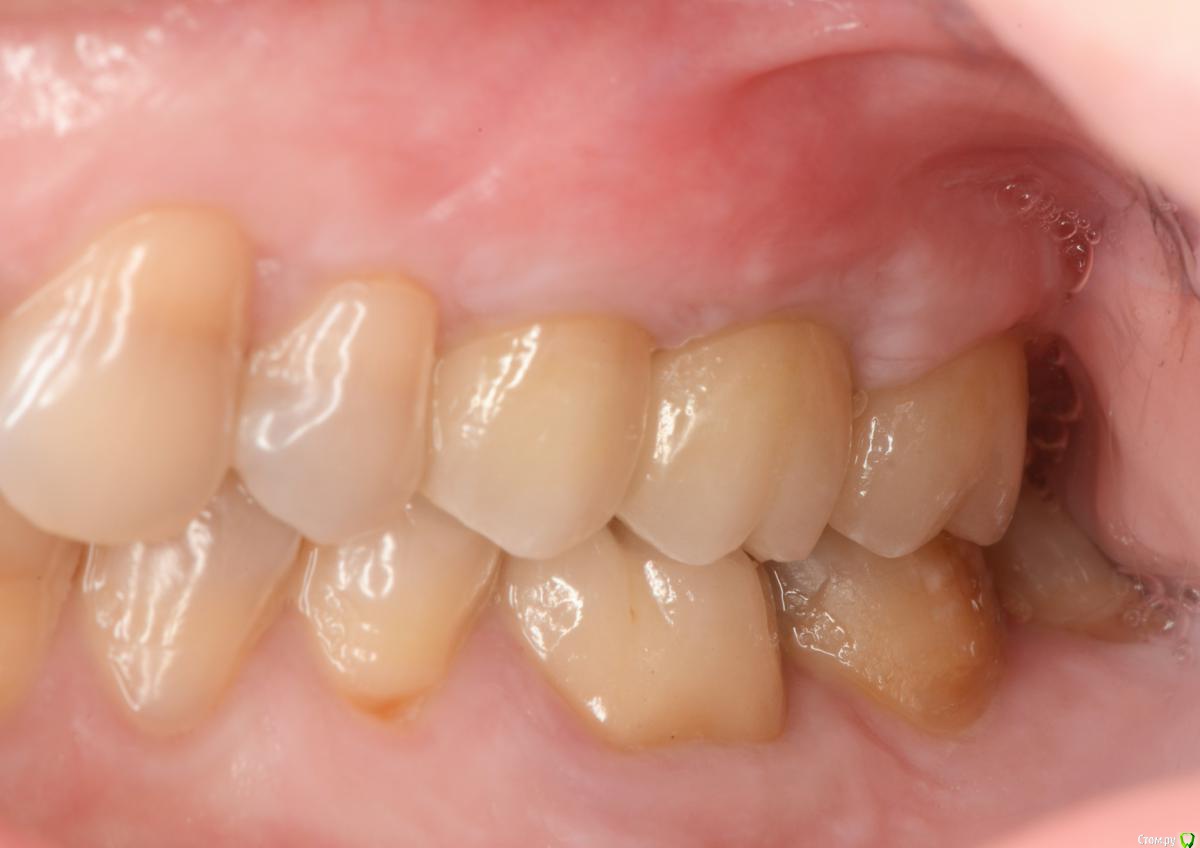

это времянки, постоянная - средний ряд, правая сторона, последнее фото

Ааа, теперь понятно. А то я думаю, почему какие-то фото отзеркалены, а другие нет... думал, что разные стороны)

Ну тогда вообще все здорово!